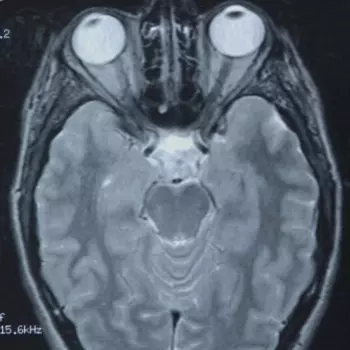

2. 윌슨병

윌슨병은 구리 대사의 이상으로 인해 주로 간과 뇌의 기저핵에 과다한 양의 구리가 축적되는 희귀 유전 질환입니다.

이 질환은 약 3만~10만 명 당 1명꼴로 발생되며, 주로 청소년기에 증상이 나타납니다. 이 증상에는 복부 팽창, 피로, 복통, 황달, 몸의 떨림 등이 포함됩니다.

윌슨병의 원인은 음식으로 섭취한 구리를 체내에서 제대로 배설하지 못하고 축적되어 문제가 발생하는 것입니다.

체내에 축적된 구리는 간과 뇌에 침입하여 간염, 정신과적, 신경학적인 증상을 유발할 수 있습니다.

간이 질환에서 가장 먼저 영향을 받으며, 축적된 구리로 인해 간세포 손상과 간경변증이 발생할 수 있습니다.

윌슨병은 간 이상뿐만 아니라 신경계, 정신과적, 안과적, 혈액, 신장, 골격, 관절통, 내분비계 등 다양한 신체 문제를 유발할 수 있습니다.